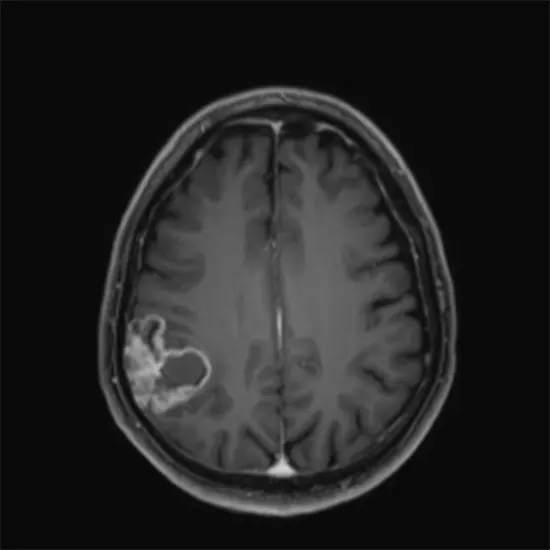

Oligodendroglioma is a type of brain tumor that arises from oligodendrocytes, which are specialized cells that produce the myelin sheath, a protective covering around nerve fibers in the central nervous system. Oligodendrogliomas are considered a type of glioma, which are tumors that originate from glial cells in the brain.

Diagnosis of oligodendroglioma usually involves a combination of medical history, physical examination, neuroimaging studies (such as MRI or CT scan), and a brain biopsy for definitive diagnosis. Molecular testing for specific genetic mutations, such as mutations in the IDH1 and IDH2 genes, is often performed to help classify the tumor and guide treatment decisions.